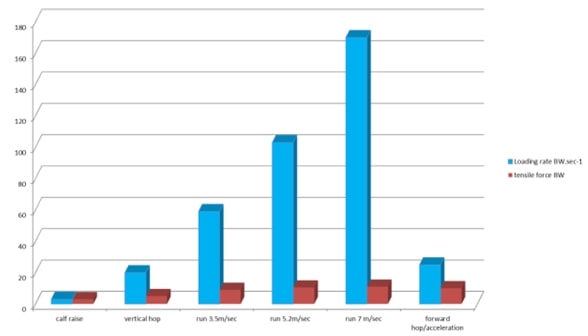

Същото се отнася и за ахилесовото сухожилие, където повдигането на прасците има много ниска степен на натоварване на сухожилието, докато бягането и скачането имат много висока степен на натоварване. Интересно е, че най-добрите спортисти, които могат да бягат бързо или да скачат нависоко, са и най-застрашените от развитие на сухожилна патология, вероятно защото могат да натоварват сухожилията си по-бързо от всички останали. Този феномен се нарича още "парадокс на коляното на скачача" и е описан в статия на Visnes et al. (2013).

Натоварване на ахилесовото сухожилие на опън и скорост на натоварване при типични дейности: